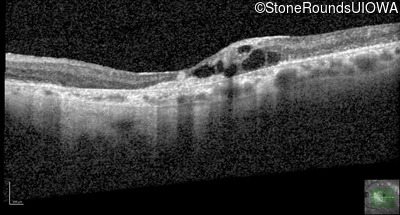

Optical Coherence Tomography - Right - 20/125 -2

Exemplar / OCT Stack

OCT Stack